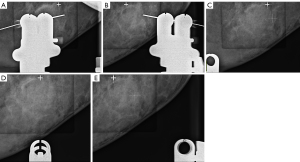

The PS-guided biopsy utilized the Siemens Mammomat Inspiration X-ray machine (Siemens, Erlangen, Germany) and a stereotactic biopsy system. This method included CNB and wire positioning. For CNB, a TSK Acecut biopsy needle (14G × 75 mm; TSK Laboratory, Tochigi, Japan) was used, whereas a Bard biopsy system needle (20G × 10.7 cm; Bard, Inc., Murray Hill, NJ, USA) was applied for wire positioning. Patients were placed in a prone position, and lesions classified as BI-RADS 4 or 5 with calcifications were selected as targets. Imaging at 0° and ±15° was performed to determine the lesion entry path, with X, Y, and Z-axis coordinates calculated based on the ±15° images (Figure 1). Typically, three exposures were required for imaging: one for the 0° image and two for the ±15° images. Additional exposure may be required during the biopsy process according to the doctor’s needs, such as determining the correct position of the biopsy needle.

After assessing the target and biopsy entry path, the skin was disinfected, local anesthesia was administered, and a 14G biopsy needle was inserted for biopsy or wire positioning. For CNB patients, X-ray imaging confirmed the retrieval of target calcification. For patients undergoing wire positioning, surgery was conducted to verify retrieval of the calcifications using X-ray imaging.